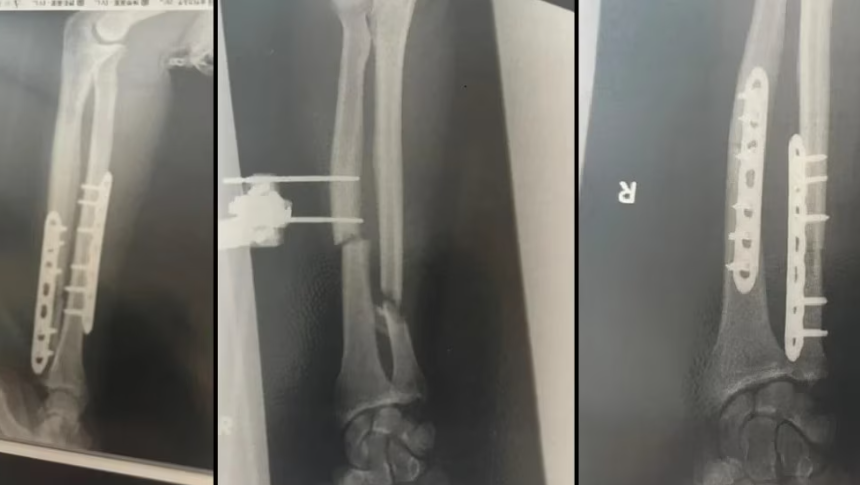

侥幸生还的Halloran用夹克暂时固定受伤的手臂,迅速跑向家中,同时拨打妻子电话求助。他家距离事发地约5分钟车程,途中救护车也赶到。他被送往距离约40分钟车程的上越医院进行救治。到目前为止,他已接受三次手术,其中一次涉及髋骨移植。Halloran称手臂有三处断裂,并有骨块被咬掉。

Billy Halloran手臂骨折X光片。供图